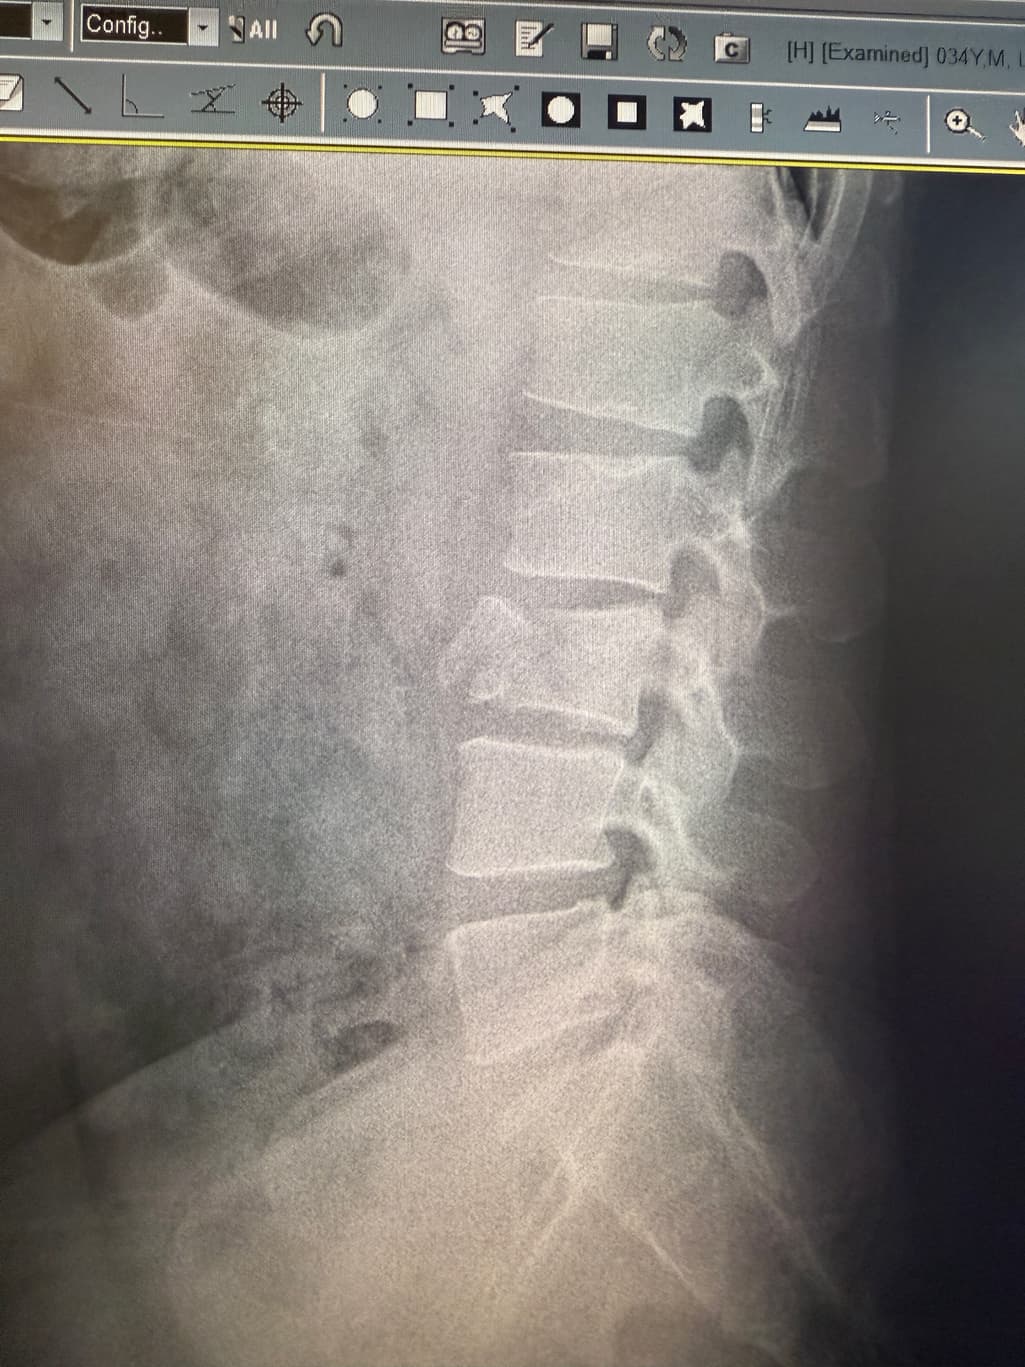

이정도면 수술해야되는거아닌가요?

척추가 저렇게 들렷는데 비수술로 그냥 굳힌다는데 추후네 디스크가 불안전하지않나요? 수술해야될거같은데..병원하나하나 믿기에 제가 부족한것같아 여기다가 한번물어봅니다 ㅠㅠ

척추가 들렸다는 것은 불안정성이나 전방 전위증 등이 의심될 수 있는데 신경 압박 증상이 없다면 보존 치료로도 충분히 관리될 수 있어요 단 통증이 지속되거나 악화된다면 수술 여부를 신중히 재검토해야 하니 척추 전문의 2차 소견도 추천드려요!

사진상 정확한 상태를 확인하기는 어려우나 척추뼈에 골절이 있는 상태로 보이며 일단 해당 병원에서 비수술적인 치료를 진행해보자고 하셨는데 불안한 상황이라면 다른 병원에 방문하시어 다른 전문의 선생님의 소견을 들어보시는 것도 좋을 것으로 생각됩니다.

병원에서 수술 없이 굳힌다고 했다는 것은 보존적 치료, 즉 물리치료나 운동요법, 혹은 코르셋 착용 등을 통한 안정화 치료를 의미할 수 있습니다. 이런 비수술적 치료는 증상이 심하지 않거나 신경 손상이 없는 경우에 우선적으로 시행되는 방법이에요

전위가 비교적 뚜렷하고, 증상이 계속되거나 악화되고 있다면 수술적 치료를 진지하게 고려해야 할 수 있습니다. 특히 다리 저림, 근력 저하, 감각 이상, 대소변 문제 같은 신경학적 증상이 있다면 수술이 필요할 가능성이 높죠

현재 치료 방식이 본인 상태에 맞는지에 대한 확신이 없다면, 척추 전문 병원에서 2차 진료를 받아보는 것이 안전하고 현명한 선택입니다. 정확한 진단과 함께 MRI 등 추가 검사로 신경 압박 정도를 확인하는 것이 치료 방향 결정에 큰 도움이 됩니다